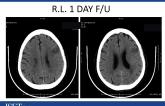

Imaging of Acute Stroke: What You Need to Make a Decision to Treat

Presentation ISET 2017

Presenter: Kevin Abrams